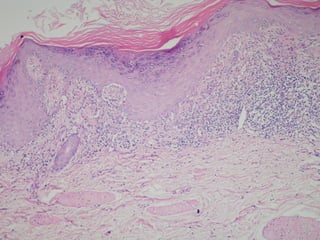

Liken Planusta epidermiste hiperkeratoz, hipergranüloz, akantoz, dermada

bant tarzında yoğun lenfosit infiltrasyonu